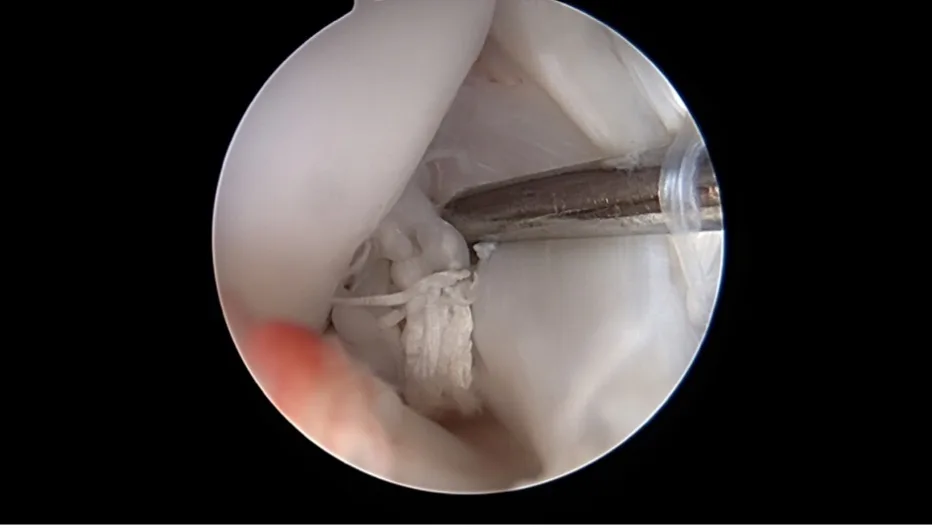

Une caméra miniaturisée permet de visualiser directement l’intérieur de l’articulation par de petites incisions cutanées. Les lésions du ligament croisé et les dommages associés comme les déchirures du ménisque peuvent être diagnostiqués et souvent traités immédiatement.

Rupture méniscale en anse de panier

Nanoscopie

Encore plus fine que l’arthroscopie, la nanoscopie utilise des instruments très petits et une imagerie haute résolution dans l’articulation. Elle est particulièrement adaptée aux petits chiens. Les deux méthodes sont mini invasives, limitent le traumatisme tissulaire et favorisent une récupération plus rapide.